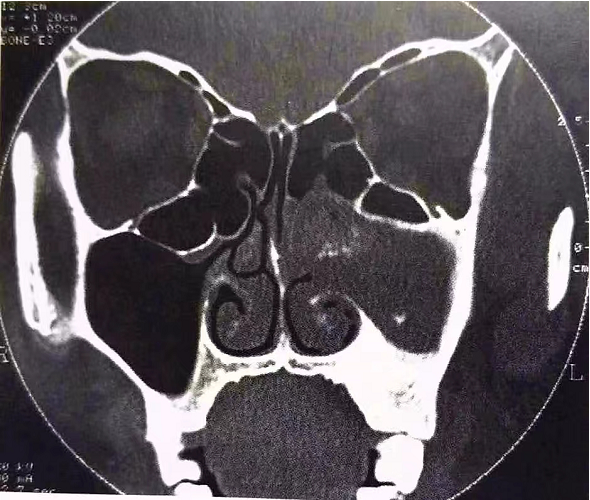

在此期間,劉女士曾到我院耳鼻咽喉科就診,通過(guò)藥物對(duì)癥治療后,癥狀有所好轉(zhuǎn)。但之后,劉女士仍舊自行用藥、輸液治療。前段時(shí)間,自感上述癥狀加重難忍后,劉女士再次來(lái)到我院就診。副鼻竇CT檢查示,左側(cè)上頜竇軟組織影,密度不均勻,近中鼻道處高密度鈣化斑,考慮真菌性上頜竇炎(左側(cè))。

(劉女士副鼻竇CT影像圖)